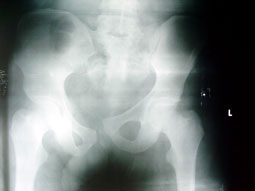

تدخل فريق جراحي بمستشفى الأمير سلمان بن عبدالعزيز من إنقاذ مصاب إثر تعرضه لحادث مروري من الشلل وهو مصاب بصدمة كبيرة نتيجة لفقده كمية كبيرة من الدم نتيجة لتعرضه لعدد من الكسور وتم اجراء عملية جراحية عاجلة عن طريق تثبيت كسور الحوض من الأمام، وذلك من خلال فتح البطن ثم فتح القلب وتم تسليك أعصاب العمود الفقري والنخاع الشوكي مع تثبيت الكسور المتفتتة بالظهر بالشرايح والمسامير وبفضل من الله قام المريض بالوقوف والمشي في اليوم الثاني.

وأوضح مدير الخدمات الطبية بمستشفى الأمير سلمان بن عبدالعزيز الدكتور عتيق القرني أن هذه العملية تعتبر هي الأولى من نوعها التي تجرى بمستشفى الأمير سلمان لوجود متخصصين جراحات كسور الحوض.